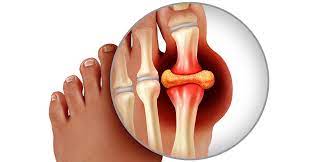

통풍은 요산이 과다로 생성되거나 요산의 배출에 장애가 발생할 경우 통풍 증상이 나타나게 됩니다.

요산이란 우리가 먹는 음식이 소화되어 최종적으로 대사하고 난 후 나오는 물질입니다. 보통 혈액 내에 녹아 있다가 소변으로 배출됩니다. 통풍 환자는 혈액 내 요산이 지나치게 많습니다. 이처럼 과다 축적된 요산은 결정체로 변하고, 이 요산 결정체가 관절 내에 침착하여 염증을 유발합니다.

통풍은 요산을 생성하는 퓨린이 다량 함유된 음식을 장기간 섭취하거나 술과 기름진 음식을 많이 섭취하여 몸 안에 요산이 축적될 경우 서구화된 식습관과 운동부족 스트레스 과다 체중 증가 등으로 인해 요산이 과다 생성되며 이들이 체외로 배출되지 못하고 관절과 힘줄 등에 쌓여 극심한 통증을 유발하게 됩니다.